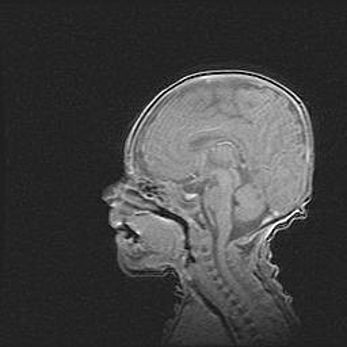

Неполная лизэнцефалия (пахигирия). Открытая гидроцефалия.

Возраст: 17 дней

Вес: 3110 г

Пол: мужской

Окружность головы: 33,5 см

Срок гестации: 35-36 недель

Лизэнцефалия—недоразвитие корковой пластинки и мозговых извилин в результате нарушения миграции нейронов коры. Поверхность мозговых полушарий гладкая. Микроскопически выявляется отсутствие нормальных слоев коры и скопление групп нейронов в подкорковом белом веществе.

Пахигирия—уменьшение числа вторичных извилин. В пораженном полушарии нервные клетки образуют толстый недифференцированный слой с неправильно расположенными нервными волокнами и группами гетеротопных клеток. Нервные клетки незрелые. Белое вещество истончено. При этом нередко аномально развит корково-спинномозговой путь.